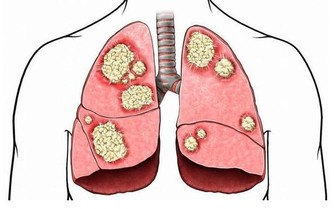

5.聲音比較響亮

我們可以從聲音洪亮不洪亮看出一個人的肺部健康情況。

如果說你的肺氣十分充足的話,那麼聲音就會十分的響亮。肺比較不少的話就會特別的無力。

6.呼吸有節奏

呼吸看似十分的簡單,但是你知道嗎?一呼一吸都跟心肝肺還有腎臟有直接的關係。

只有呼吸比較平穩有節奏的話,那麼就證明你的心肝肺腎的功能比較好。